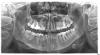

Nastya88 Опубликовано 5 апреля, 2009 Поделиться Опубликовано 5 апреля, 2009 Здравствуйте! Два с половиной года назад у меня были проблемы с верхней 6-кой. Зуб хотели удалять, т.к. он очень запущен был,но всё-же вылечили, но без гарантии. Зуб очень болел, была киста. Корни запломбировали. Киску лечили лазером (если я не ошибаюсь) в течение дней десяти (каждый день ходила к врачу). Всё прошло. Четыре дня назад поставила брекеты. Боль начала жуткая в районе как раз того самого зуба. Пью обезбаливающие (кетарол, нурофен). Помогает, но боль не снимает полностью, просто утихает боль. Как раз на этот зуб ортодонт еще и кольцо одела. Вопрос такой: с чем эта боль связана - в связи с утановкой брекетов (слышала, что тянет первые дни) или всё-же дала о себе знать та киста? И если это всё-таки киста, то что же тогда делать в такой ситуации, брекеты что-ли снимать? И что теперь делать с этим зубом, что такое может болеть, если зуб без нерва итак? Для наглядности выкладывают снимок. Сделан 5 дней назад. Зуб шестой верхний, на фото справа. Заранее спасибо за ответ! Очень надеюсь на вашу помошь. Ссылка на комментарий

Anvik Опубликовано 6 апреля, 2009 Поделиться Опубликовано 6 апреля, 2009 Доброй ночи! Я бы посоветовал сделать еще прицельный снимок, однако мне таки кажуться изменения вокруг корней этой 6-ки! Чессно слово - зуб лучше удалить и потом на его место имплант поставить. С уважением,Алексей. Ссылка на комментарий

Orthodoc Опубликовано 7 апреля, 2009 Поделиться Опубликовано 7 апреля, 2009 Здравствуйте! Два с половиной года назад у меня были проблемы с верхней 6-кой. Зуб хотели удалять, т.к. он очень запущен был,но всё-же вылечили, но без гарантии. Зуб очень болел, была киста. Корни запломбировали. Киску лечили лазером (если я не ошибаюсь) в течение дней десяти (каждый день ходила к врачу). Всё прошло. Четыре дня назад поставила брекеты. Боль начала жуткая в районе как раз того самого зуба. Пью обезбаливающие (кетарол, нурофен). Помогает, но боль не снимает полностью, просто утихает боль. Как раз на этот зуб ортодонт еще и кольцо одела. Вопрос такой: с чем эта боль связана - в связи с утановкой брекетов (слышала, что тянет первые дни) или всё-же дала о себе знать та киста? И если это всё-таки киста, то что же тогда делать в такой ситуации, брекеты что-ли снимать? И что теперь делать с этим зубом, что такое может болеть, если зуб без нерва итак? Для наглядности выкладывают снимок. Сделан 5 дней назад. Зуб шестой верхний, на фото справа. Заранее спасибо за ответ! Очень надеюсь на вашу помошь.Обязательно сделайте прицельный снимок. Киста, по-моему, осталась на месте. В таком случае зуб подлежит удалению. Его участие в смещениях зубов может привести к быстрому разрастанию кисты, а рядом гайморова пазуха... Ссылка на комментарий

Dr. Surkin Опубликовано 7 апреля, 2009 Поделиться Опубликовано 7 апреля, 2009 Доброй ночи! Я бы посоветовал сделать еще прицельный снимок, однако мне таки кажуться изменения вокруг корней этой 6-ки! Чессно слово - зуб лучше удалить и потом на его место имплант поставить. С уважением,Алексей. А я чего-то ничего там страшного не вижу...Но прицельный снимок не помешает.. Ссылка на комментарий